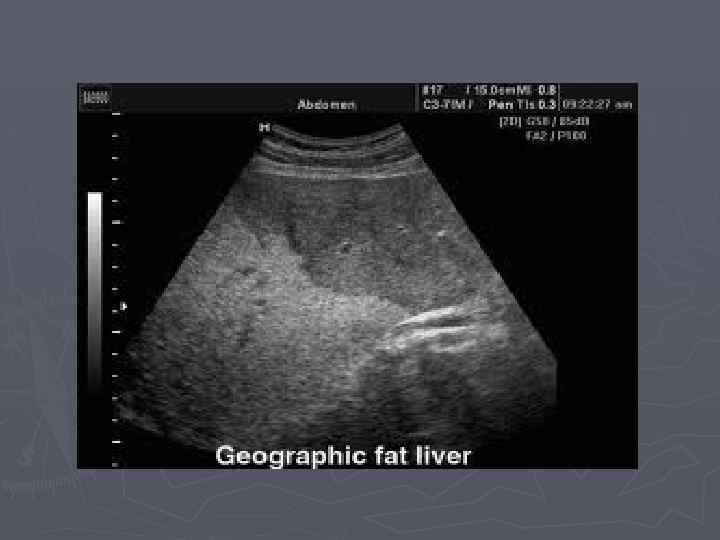

Майлы паренхималық дистрофия деп жасуша цитоплазмасында майдың көбейіп кетуін, кейде майдың қалыпты жағдайда кездеспейтін жерлерде пайда болуын немесе химиялық құрамы басқаша майлардың жиналып қалуын түсінеміз. Жасушада негізінен үшглицеридтер, холестерин эфирлері және фосфолипидтер жиналады.

Майлы паренхималық дистрофия деп жасуша цитоплазмасында майдың көбейіп кетуін, кейде майдың қалыпты жағдайда кездеспейтін жерлерде пайда болуын немесе химиялық құрамы басқаша майлардың жиналып қалуын түсінеміз. Жасушада негізінен үшглицеридтер, холестерин эфирлері және фосфолипидтер жиналады. Нәтижесінде бауырдың көрінісі мынадай болады;

Бауырдың майлы дистрофиясы Бауыр май алмасуы үрдісіне тікелей қатысатын ағза болғандықтан бұл жерде гистохимиялық реакциялар арқылы әрдайым май тамшыларын табуға болады. Сондықтан, бауырдың майлы дистрофиясы дегенде біз осы жердегі май мөлшерінің әдеттегіден көбейіп кетуын немесе химиалыық құрамы басқаша болған майлардың жиналып қалуын түсінеміз. Жасуша ішіндегі үшглицеридтер бауырдан шығып кетуі үшін апопротеин молекуласымен қосылып, липопротеин түзеді.

► Бауырдың майлы дистрофиясы улы заттар әсерінде, алкоголизмде, қантты диабетте, семіздікте, белоктық заттардың жетіспушілігіне байланысты дамиды